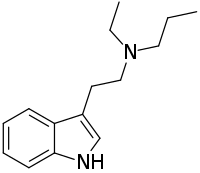

| DET | artificial | H | CH2CH3 | CH2CH3 | N,N-diethyltryptamine | 61-51-8 |

| EPT | artificial | H | CH2CH3 | CH2CH2CH3 | N-Ethyl-N-propyltryptamine | 850032-68-7 |